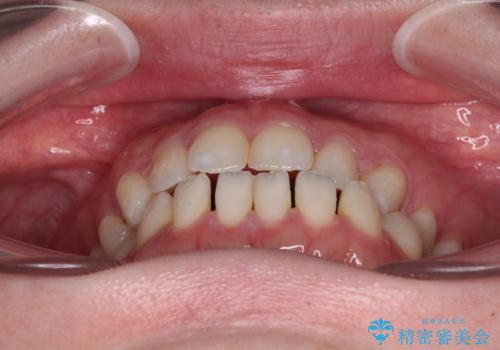

すきっ歯をインビザラインできれいな歯並びに改善

- 前歯の隙間を気にして来院された患者様です。

隙間や叢生の程度はそれほど著しいものではなかったので、インビザラインでもワイヤー矯正でも対応可能でしたが、極力目立たない装置を希望されたため、インビザラインにて矯正治療を行うこととしました。